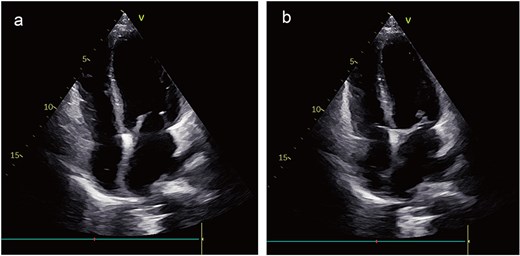

During surveillance at 3 years postoperatively, echocardiography showed no local recurrence; however, chest CT identified multiple pulmonary nodules suggestive of metastatic disease. Genetic profiling demonstrated PD-L1 positivity, prompting initiation of immunotherapy with tislelizumab. At the 4-year follow-up, the patient remained clinically stable with no echocardiographic evidence of local recurrence (Fig. 6a and b) and continues under close monitoring.

Postoperative images. The echocardiogram indicated no signs of local recurrence (a) and (b).